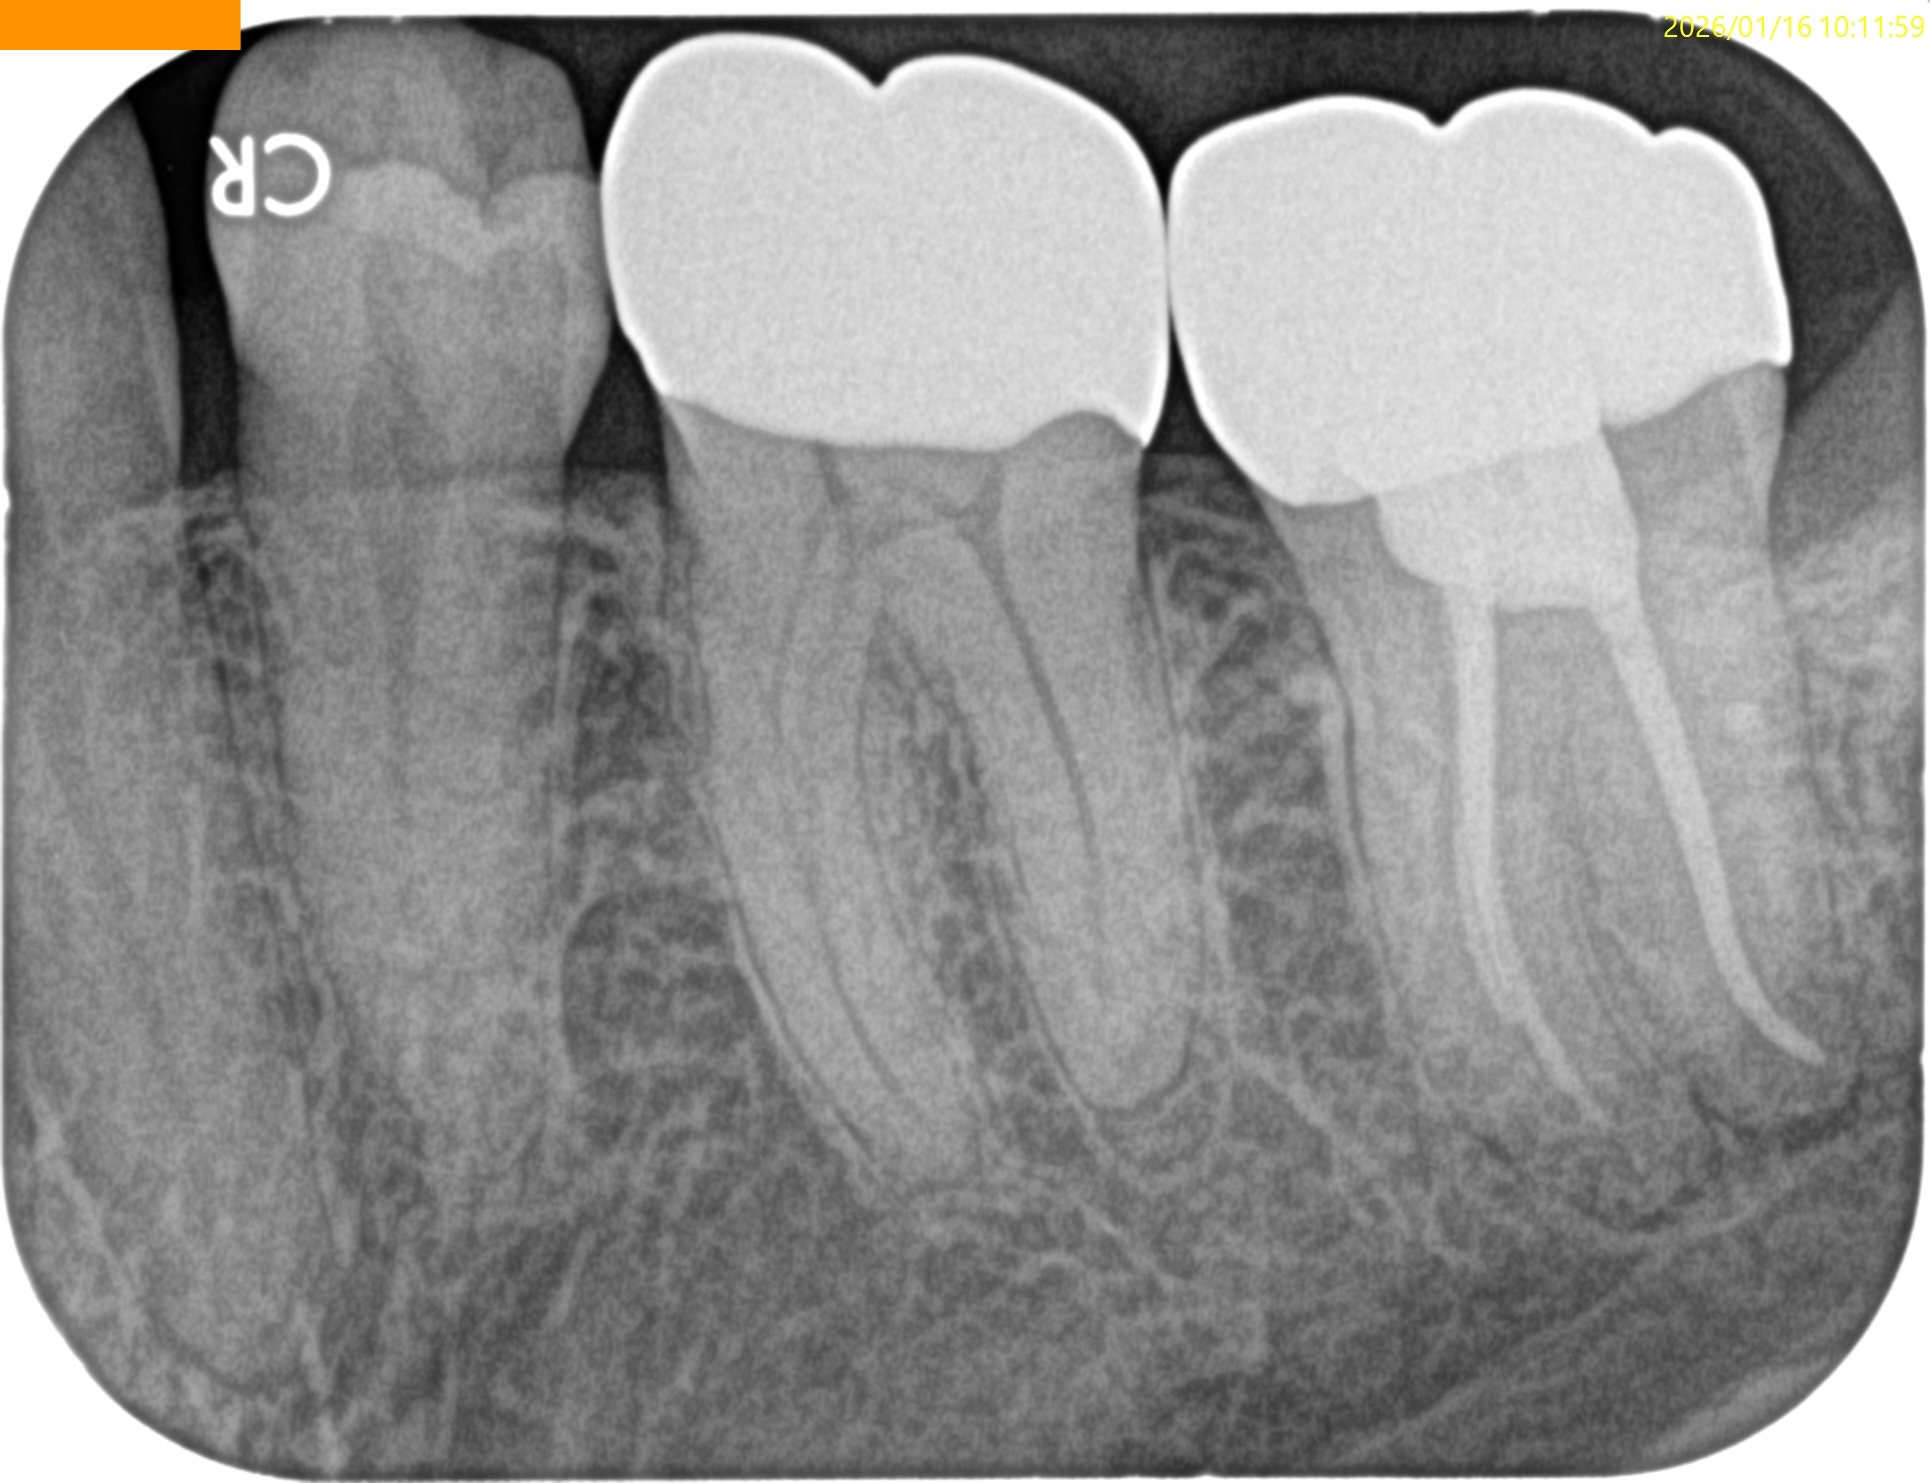

#18 RCT 1yr recall(2026.1.16)

MB

ML

D

1年経過して初診時の臨床症状、根尖病変の発現はないので経過観察も終了とさせていただいた。